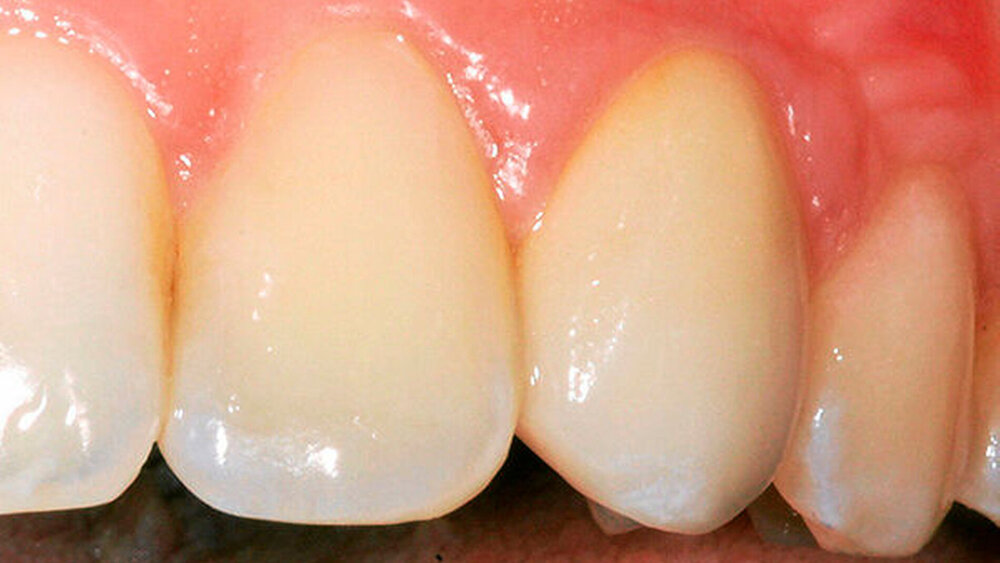

Auf jeden Fall! Neben einer besseren Ästhetik, gerade bei der Verwendung von Zirkon, ist die Lage des Übergangs Abutment-Krone bei zementierten Arbeiten von enormer Wichtigkeit. Werden aufgrund zu tief subgingival liegender Kronenränder Zementreste unzureichend entfernt, stellt dies eine der Hauptursachen für eine frühe Periimplantitis dar.

Definitiv. Bis kurz vor der Herstellung der Restauration kann ich entscheiden, ob ich das Abutment einteilig als Hybridkrone oder zweiteilig gestalte. Zudem ist ein Materialmix möglich: Aus Zirkonoxid plus Kunststoff lassen sich Langzeitprovisorien fertigen, das individuelle Kompositabutment kann man nach drei Monaten austauschen, um die Gingiva auszuformen. Oder man bleibt bei Lithiumdisilikat und setzt auf einteilige Hybridkronen.